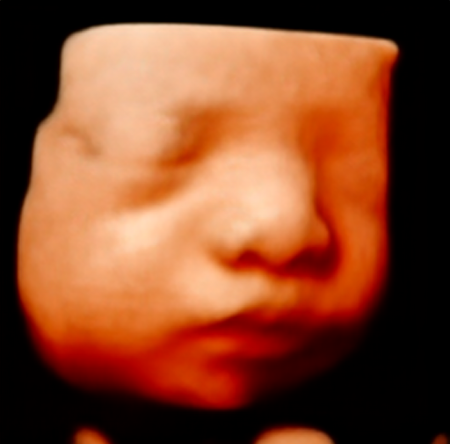

다시 볼 땐 가만히 얼굴을 잘 보여준 뚝딱이!!

모야모야ㅠㅠ 너무 귀엽잖아ㅠㅠ

입체초음파만 보고 누굴 닮았는지 나는 잘 모르겠던데

사람들은 눈 하고 입은 나를, 코는 남편을 닮은 것 같다고 했다.ㅎㅎ

이쁘고 건강하게 태어나기만 해 주라!!ㅎㅎㅎ